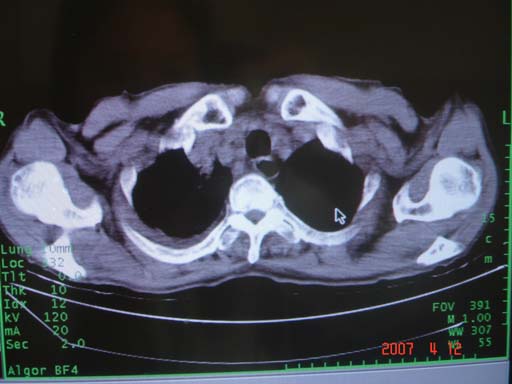

为何只有这么几幅图像?连纵隔窗都没有。但我发现上叶支气管显示不清,再加上年纪大,咯血等症状,恶性肿瘤首先得考虑。

1考虑中央型肺癌纵隔淋巴结转移。

右肺上叶后段支气管中断,首先考虑中央型肺癌并右肺不张及纵隔淋巴结转移,右侧胸腔积液。

为何只有这么几幅图像?连纵隔窗都没有。但我发现上叶支气管显示不清,再加上年纪大,咯血等症状,恶性肿瘤首先得考虑

考虑右侧中央型肺癌伴中上肺阻塞性肺炎、不张,淋巴结肿大,胸腔积液。,建议支纤镜检查